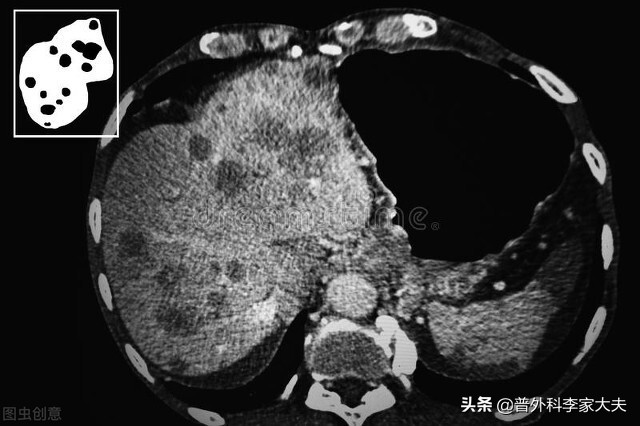

肝癌

从保护肝脏功能的角度来考虑:

肝脏承担着人体的胆汁分泌、代谢功能、解毒与吞噬或免疫作用等,对于肝癌晚期患者来说,患者的肝脏储备功能有限,甚至因为肝癌疾病原因,会导致患者肝功能不好。因此,避免高脂饮食,给患者带来的肝脏胆汁分泌负荷太重的问题,也要避免高蛋白饮食,给患者带来的血氨代谢障碍,而增加肝性脑病发生。同时,还要避免高糖饮食或不均衡饮食,给患者肝脏带来的糖代谢异常与其他物质代谢负担过重问题。另外,尽可能排除有毒外来物或进入人体会产生毒素的食物进食, 以减少它们给肝脏带来的解毒负担。宜少吃多餐、注意均衡营养饮食,提供患者肝脏能够承担的饮食代谢负荷,来进行营养物质的进食。